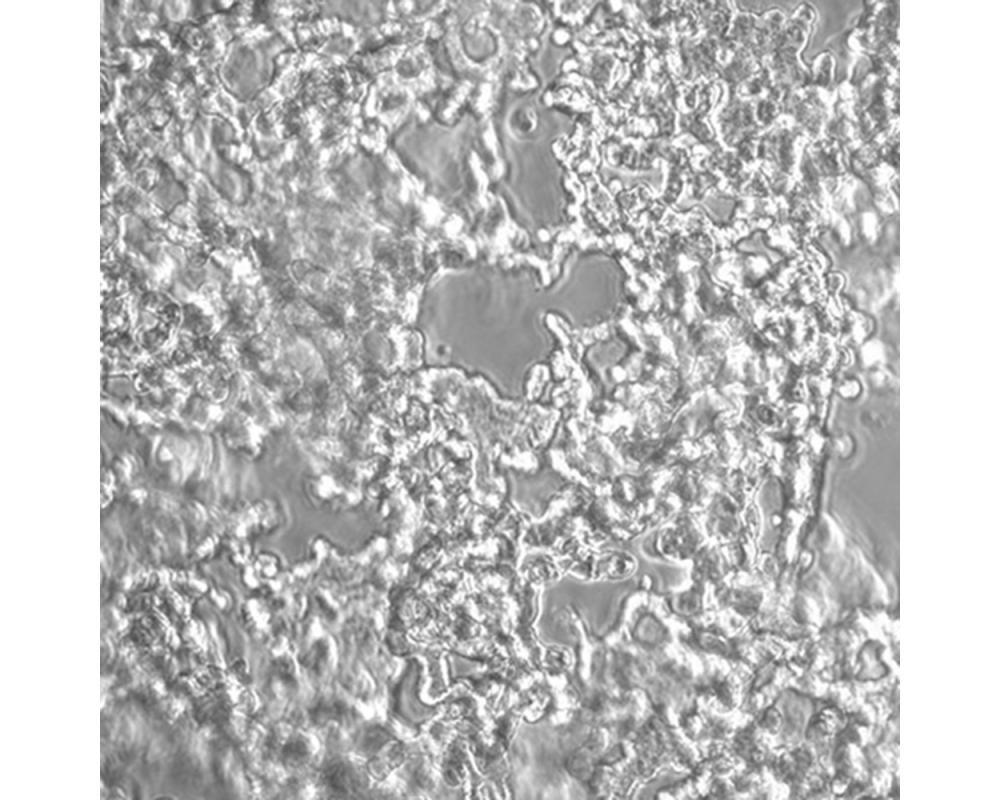

NCI-H526

產(chǎn)品名稱 NCI-H526

中文名稱 人小細(xì)胞肺癌細(xì)胞

組織來源 小細(xì)胞肺癌;骨髓轉(zhuǎn)移;男性

生長(zhǎng)特性 懸浮